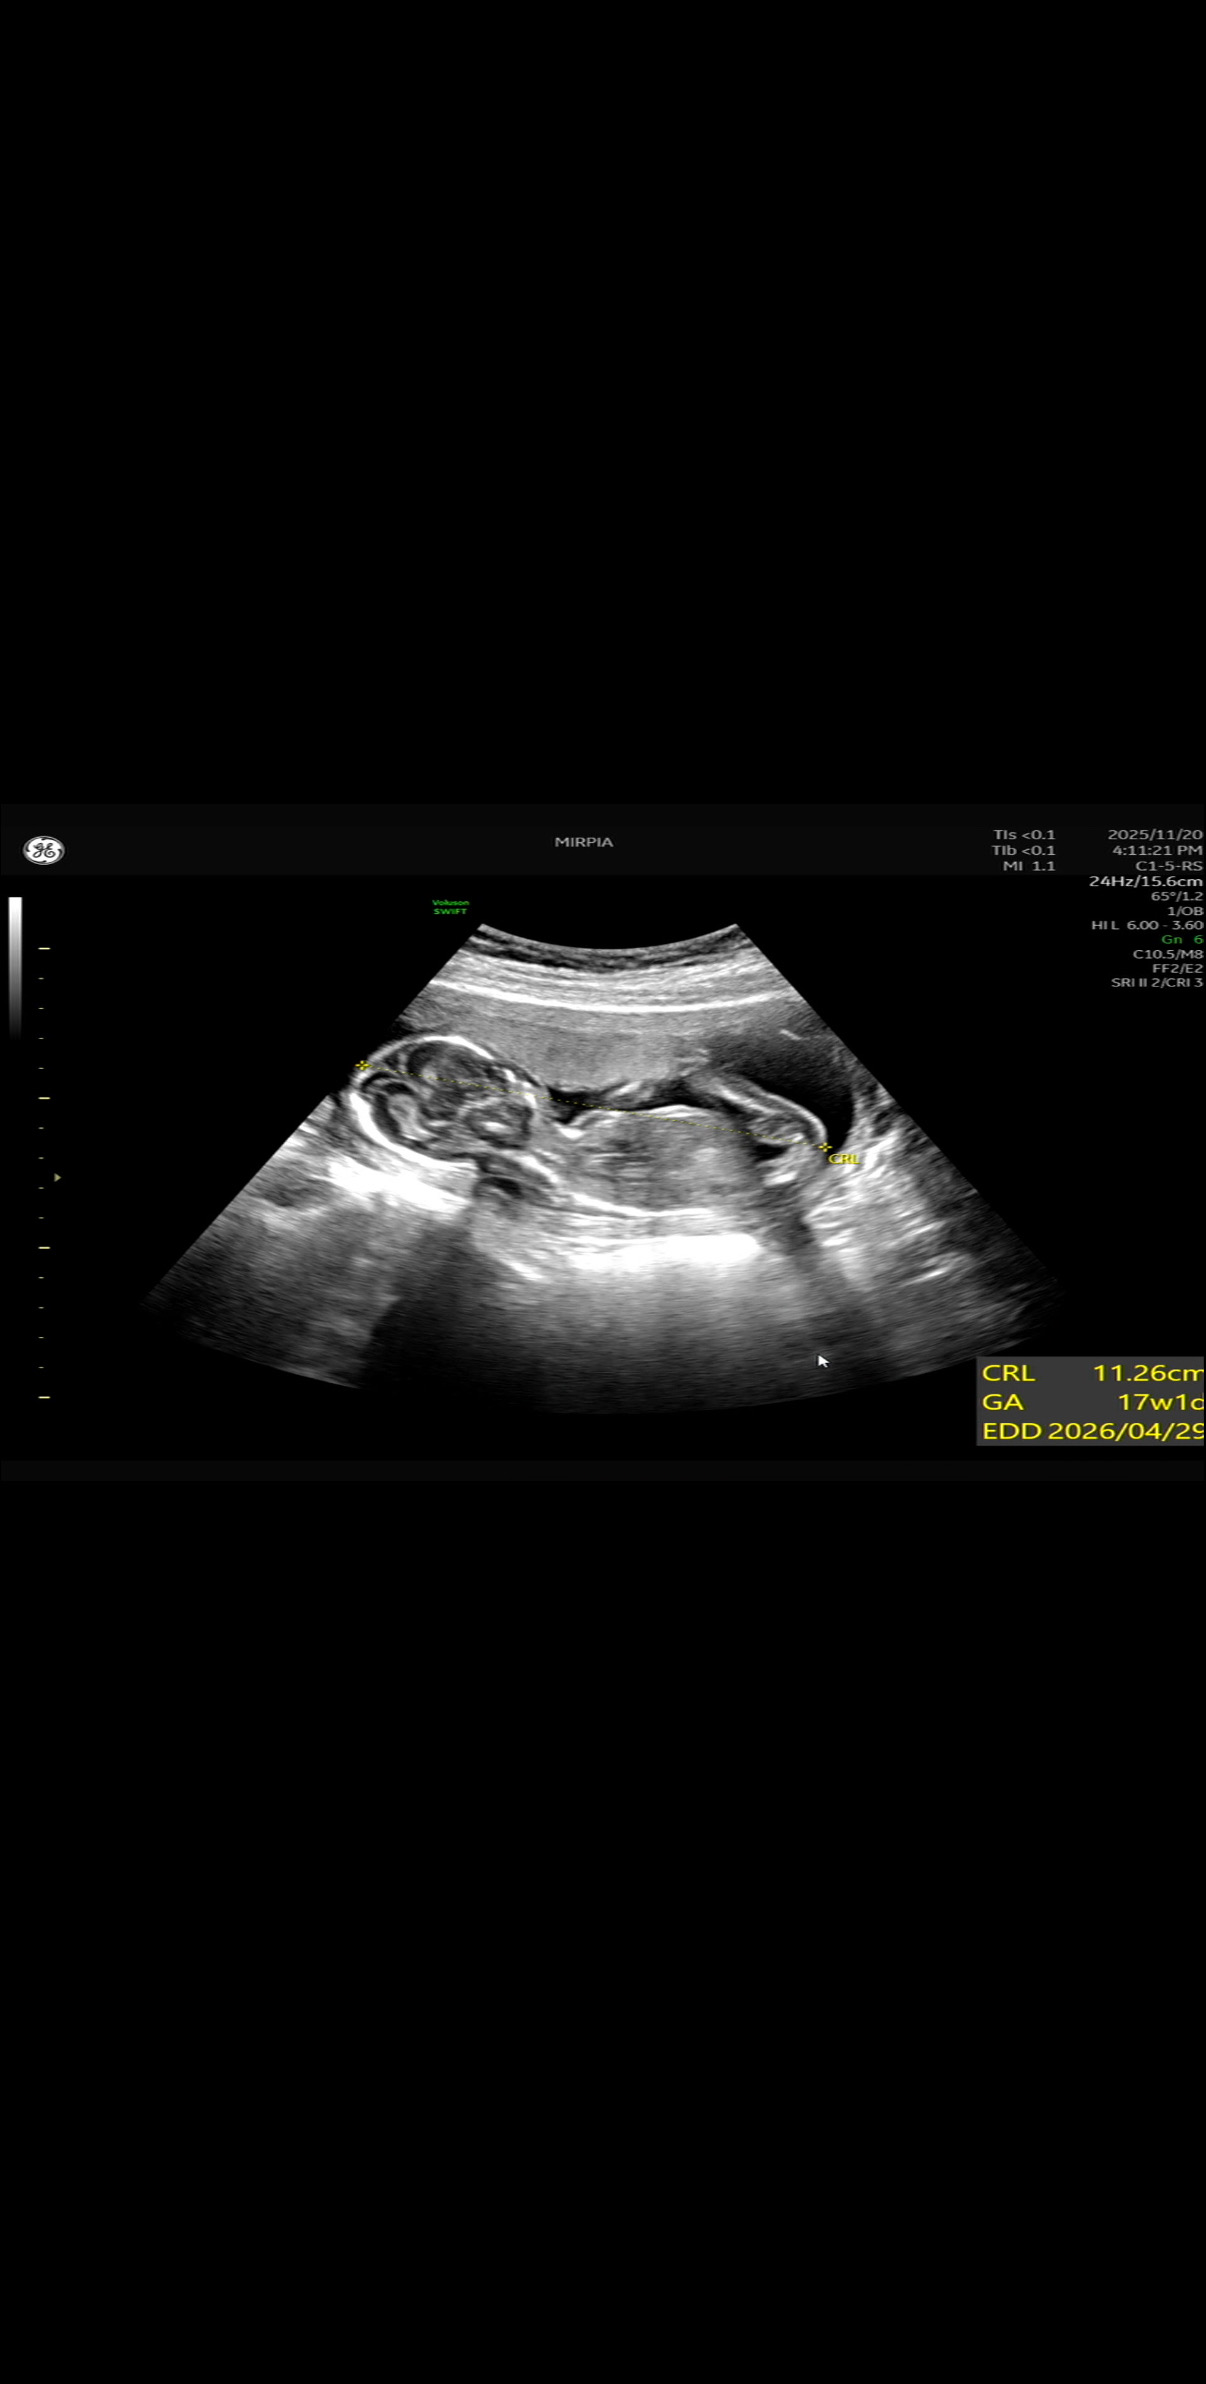

어제 성별 확인했는데 그냥 봐도 너무 선명한 아들이더라고요ㅎ